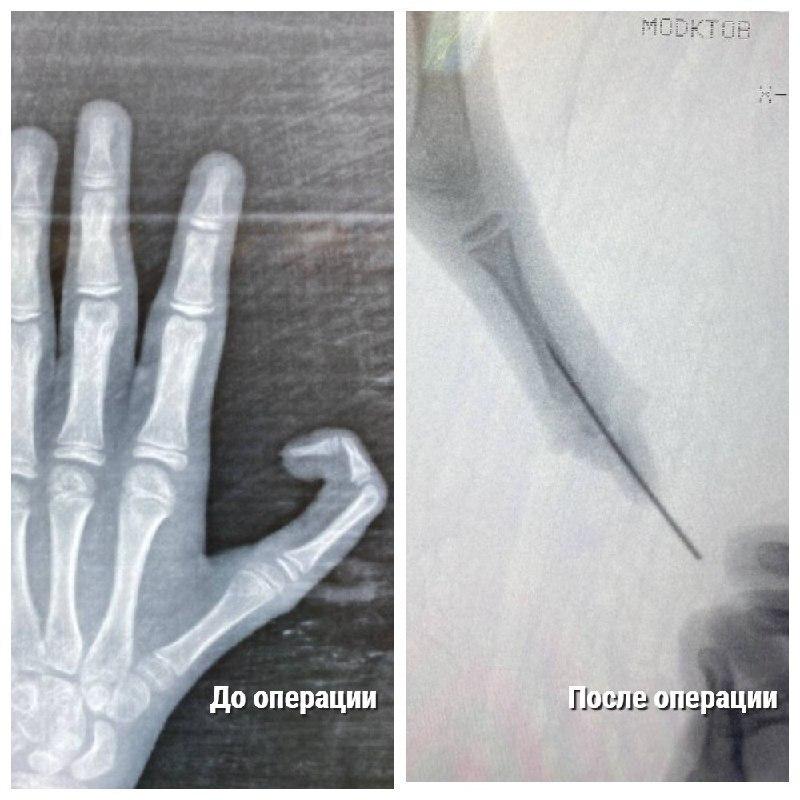

Как быстро помочь при переломе пальца: что нужно знать